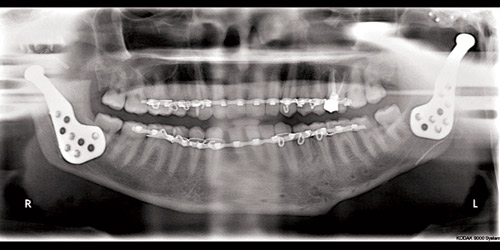

نجح فريق جراحة الوجه والفكين في مدينة الملك فهد الطبية في إتمام عملية نادرة ومعقدة لزراعة مفصل فك تعويضي صناعي لمريض سعودي في العقد الثالث من العمر، مكنه من إعادة فتح الفم والقدرة على الكلام والحركة وممارسة حياته، بعد فشل كل المحالات الجراحية السابقة.

وكان المريض قد تعرض لحادث، أدى إلى كسور في الفك والمفصل الصدغي؛ ما نتج منه التحام الفك السفلي بقاع الجمجمة، فأجرى عددًا من العمليات في مستشفيات عدة غير متخصصة لفتح الفك وإزالة الالتصاقات، ولكن كانت تعود له لما في الجراحة التقليدية من حاجة إلى عمل تمارين لمنع عودة الالتحام العظمي لمدة لا تقل عن 6 أشهر.